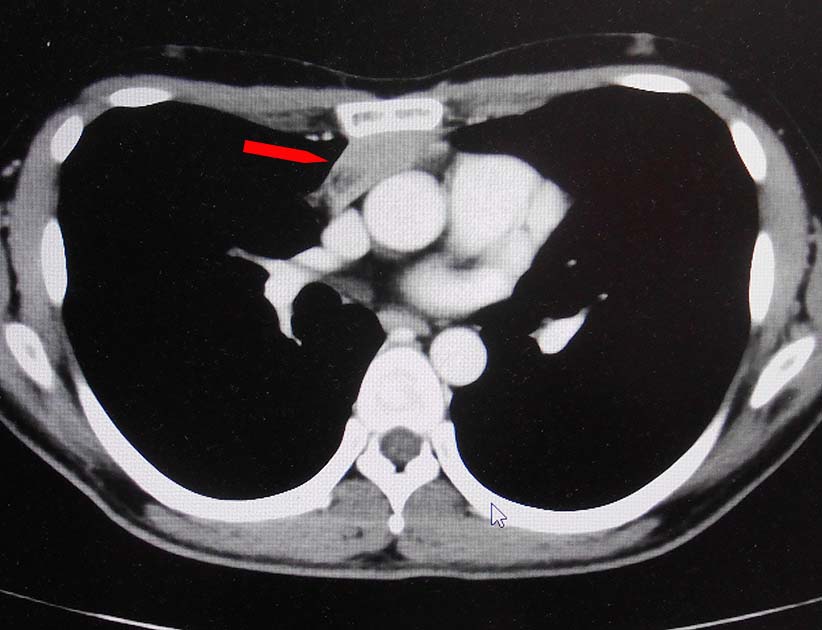

前縦隔や右心横隔膜角部に不定形, 不均一でべたっとした腫瘤状軟部濃度域を認める. 節外浸潤を伴ったリンパ節転移の可能性を考える.

画像: 左精巣腫瘤. 縦隔リンパ節転移疑い.